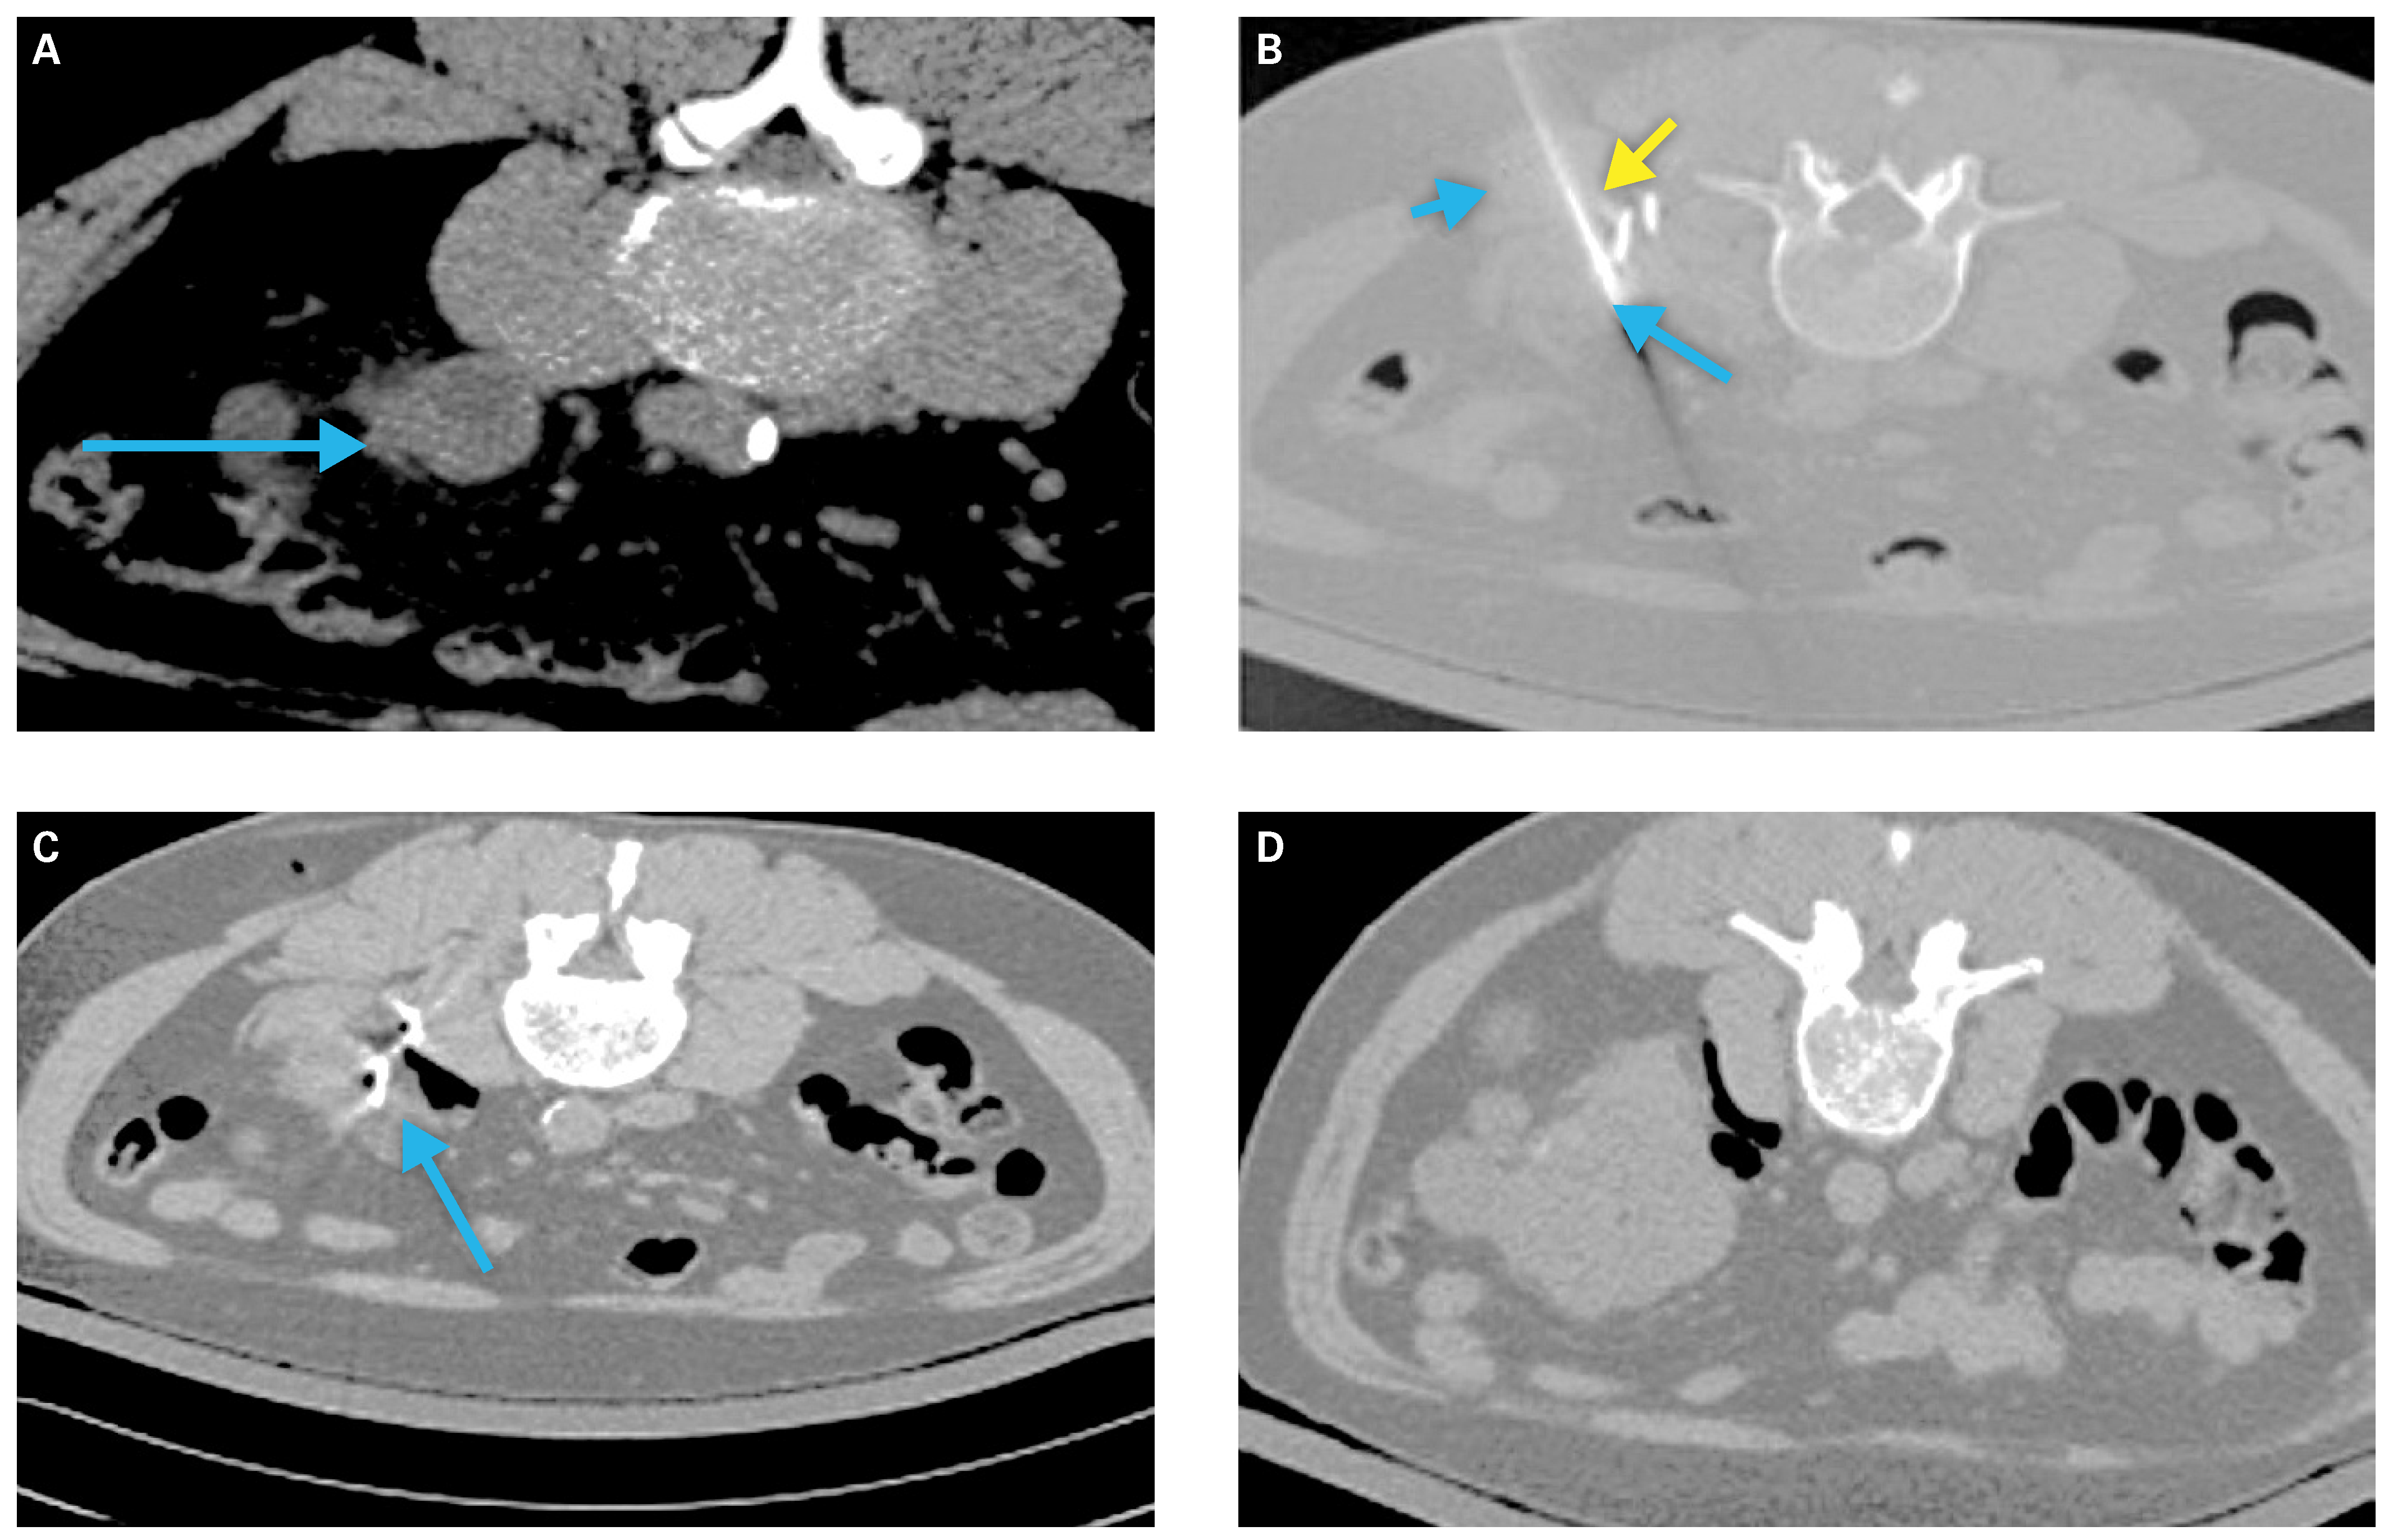

Technical Considerations

Preprocedural Planning